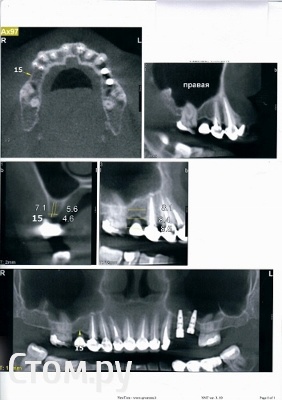

Инна Михайловна Опубликовано 14 ноября, 2014 Поделиться Опубликовано 14 ноября, 2014 Добрый день, уважаемые доктора! Буду очень признательна за ответ на мою тему. Хочу установить имплантат на верхнюю 5-ку справа. Консультировалась у трех докторов. 1 доктор решил сделать в одну оперцию синус-лифтинг с костной подсадкой и установкой импланта2 доктор - сделать костное наращивание. И только через несколько месяцев установить имплант.3 доктор- сделать наращивание кости сразу с установкой импланта длиной 8 мм.Я поняла, что у меня недостаточная ширина кости, высота говорят около 8 мм, это на КТ. У меня 2 КТ, одна на диске, ее пока не могу отослать, а фото отправляю. У меня слева стоят 2 импланта Нобель. Важно ли с другой стороны ставить такой же или же можно израильский Мис? Ссылка на комментарий

SDC Опубликовано 14 ноября, 2014 Поделиться Опубликовано 14 ноября, 2014 (изменено) Добрый день, уважаемые доктора! Буду очень признательна за ответ на мою тему. Хочу установить имплантат на верхнюю 5-ку справа. Консультировалась у трех докторов. 1 доктор решил сделать в одну оперцию синус-лифтинг с костной подсадкой и установкой импланта2 доктор - сделать костное наращивание. И только через несколько месяцев установить имплант.3 доктор- сделать наращивание кости сразу с установкой импланта длиной 8 мм.Я поняла, что у меня недостаточная ширина кости, высота говорят около 8 мм, это на КТ. У меня 2 КТ, одна на диске, ее пока не могу отослать, а фото отправляю. У меня слева стоят 2 импланта Нобель. Важно ли с другой стороны ставить такой же или же можно израильский Мис?Можно устанавливать имплантат любого производителя, не важно соответствие марки. Иногда бывает сложнее с протезированием, когда в клинике есть все для Нобеля и ничего для Мис и наоборот, но не большая проблема.В данном случае я бы планировал имплантацию с закрытым синус-лифтингом, одномоментно. длина имплантата 8-11 мм. Изменено 14 ноября, 2014 пользователем SDC Ссылка на комментарий

SDC Опубликовано 15 ноября, 2014 Поделиться Опубликовано 15 ноября, 2014 Добрый день! От всей души благодарю ВАС за скорый ответ!!!! А что скажете по толщине кости, нужна подсадка? И если поставить 8 мм имплант, то все равно обязателен синус-лифтинг?Наблюдается небольшой дефицит косной ткани по ширине, что может быть решено проведением направленной костной регенерации одномоментно с имплантацией. И даже для 8 мм. имплантата необходим небольшой закрытый синус-лифтинг.Без синус-лифтинга возможна установка 6 мм. имплантата. В принципе, этот вариант может быть рассмотрен для исполнения, короткие имплантаты (6 - 8 мм) показывают достаточно хорошие результаты в отдаленном периоде. Ссылка на комментарий